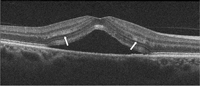

Figura 2. Hallazgos en la coroidorretinopatía serosa central aguda. Se aprecia un desprendimiento neurosensorial, con disminución de la capa nuclear externa. La membrana limitante externa aparece conservada. Existe un alargamiento de los fotorreceptores y una alteración de la capa elipsoide (flechas blancas).

Figura 3. A) Varón joven con coroidorretinopatía serosa central aguda. B) Se aprecia un gran desprendimiento de la retina neurosensorial con afectación foveolar. En el corte tomográfico se muestra un desprendimiento localizado del epitelio pigmentario con la doble imagen epitelio pigmentario-membrana de Bruch y material hiporreflectivo entre ellas. C) La angiografía objetiva cómo el desprendimiento del epitelio coincide con el punto de fuga. D) Resolución espontánea del desprendimiento neurosensorial a los 2 meses.

Es frecuente observar pequeños desprendimientos del epitelio pigmentario (

Figura 3B), que suelen corresponder a puntos de fuga en la angiografía. Se especula que son el origen de la enfermedad, aunque no se conoce con exactitud el mecanismo por el que se forman. Estos desprendimientos del epitelio pigmentario de la retina suelen asociar una imagen doble de EPR-membrana de Bruch, con material normalmente hiporreflectivo entre estas capas